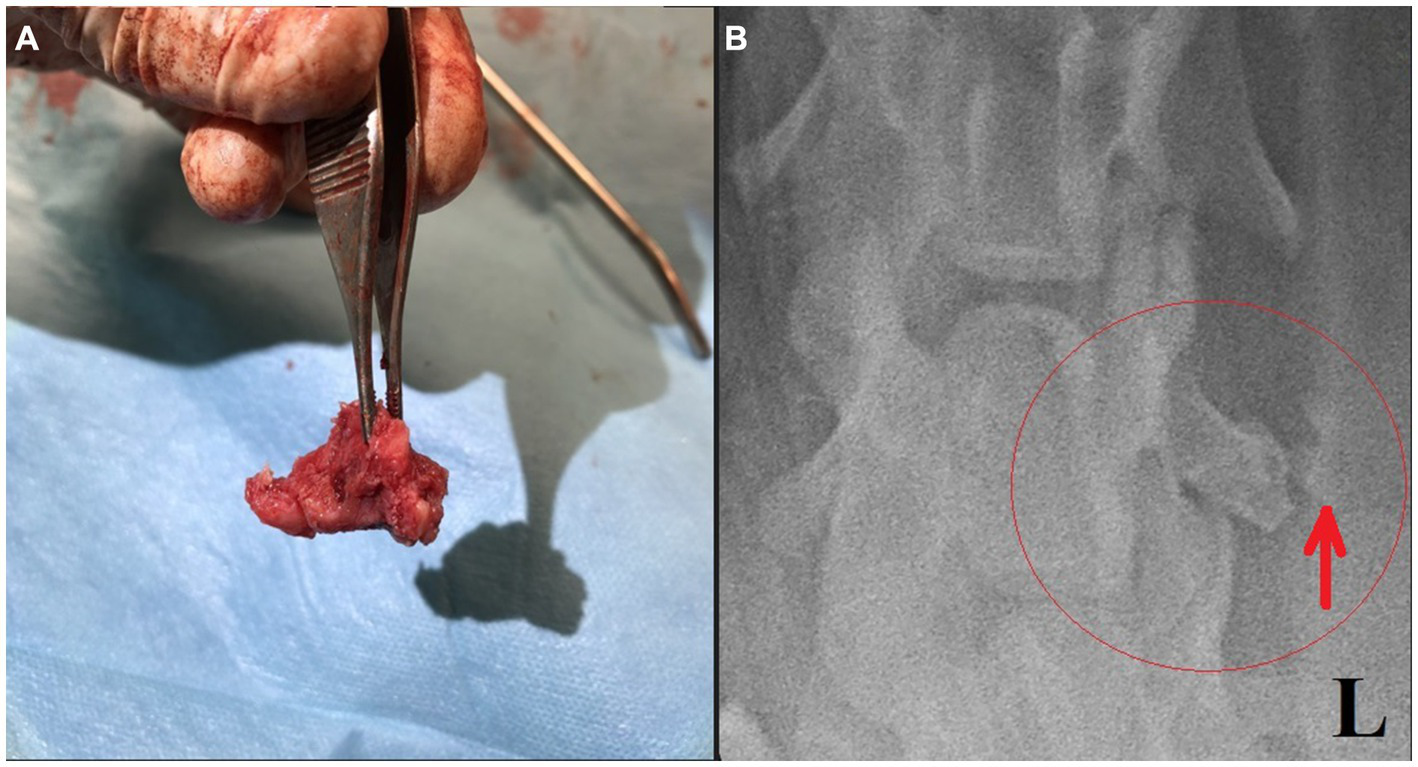

Surgery was performed. The patient was placed in right lateral recumbency with thoracic limbs tied caudally; a skin incision was made over the mass, and the sternohyoideus and sternooccipitalis muscles were retracted. First, the firm capsule over the osseous mass was dissected. The fluid was drained, and the bony structure was exposed. Fluid and tissue samples from the lesion were submitted for aerobic and anaerobic cultures that had negative growth. The lesion was attached to the latissimus cervicis muscle and had loose, fibrous attachment to the left transverse process of the C5 vertebra. The left C6 spinal nerve was embedded in the osseous mass. The mass was dissected, freed from the fibrous attachment, and removed as one piece. The entrapped spinal nerve was meticulously and gently dissected, freed, and cleared from the osseous mass. The tissues at the site were sutured, and the wound was closed routinely. The excised tissue was submitted for histopathological examination. It measured 12 × 18 × 12 mm and appeared partially encapsulated with an irregular surface and white to light brown color. It was firm and gritty to cut (Figure 2A). Staining techniques used were hematoxylin–eosin (HE) and Giemsa. Microscopically, it presented as a well-circumscribed partially encapsulated, multiloculated formation of fully differentiated woven bone fading into more mature lamellar bone. Bone spicules were coated by a hypercellular osteoblastic lining peppered with some osteoclasts. The endosteal compartment showed central hematopoietically active red bone marrow. The capsule consisted of thick bundles of parallel-oriented, poorly cellular fibrocollagenous tissue that came into direct contact with lamellar bone. Along the capsule, there was a marked proliferation of blood vessels, both arteries and veins, with occasional cavernous spaces filled with amorphous, slightly eosinophilic material, and a variable amount of intraluminal red blood cells resembling vascular hamartoma. The blood vessel walls appeared moderately thickened, with prominent smooth muscle cells. Oligofocal metaplastic cartilage formation was observed in one section. The skeletal muscle outside the capsule appeared mild to moderately atrophic without evidence of inflammatory infiltrates. The morphological diagnosis was an intramuscular, mature HO with vascular hamartoma (Figure 3). Post-surgery radiographs detected a dense residual tissue (suspected to be the rest of the firm capsule), confirming that HO had probably not been completely removed (Figure 2B). Within 1 month post-surgery, the lameness fully resolved. Two years later, an osseous lesion of 8 mm in size was detected on routine follow-up radiographs at the surgery site; however, there were no associated clinical signs (Figure 4). Neurological examination findings at these follow-up time points were normal.

Figure 2

(A) Removed bony structure. (B) Post-surgical ventrodorsal radiograph of the cervical region with a small amount of residual tissue suspected incomplete lesion capsule removal (red ellipse and arrow).